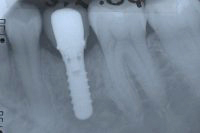

Ein aus der Kindheit stammender Milchzahn ohne Wurzeln im Seitenzahngebiet (Abb. 1), der eiterte und gezogen werden musste, hinterliess bei einer 37 Jahre alten Patientin eine grosse Lücke, aber gesunde Nachbarzähne. Um die Lücke mit einem festsitzenden Zahnersatz zu schliessen, setzen wir ein Zahnimplantat (Abb. 2 und 3). Das Setzen einer Zahnbrücke wäre ebenfalls möglich gewesen, hätte aber das Beschleifen der gesunden Nachbarzähne erfordert, was wir vermeiden wollten.

Sechs Wochen später, nach Einheilung des Implantates (Abb. 2), wird ein Aufbau aus Titan ins Implantat geschraubt (Abb. 3). Nach Abdrucknahme fertigt der Zahntechniker eine Krone an (in diesem Fall eine Vollporzellankrone), die auf dem Implantatpfosten einzementiert wird (Abb. 4). In Abb. 5 ist das Schlussröntgenbild zu sehen.